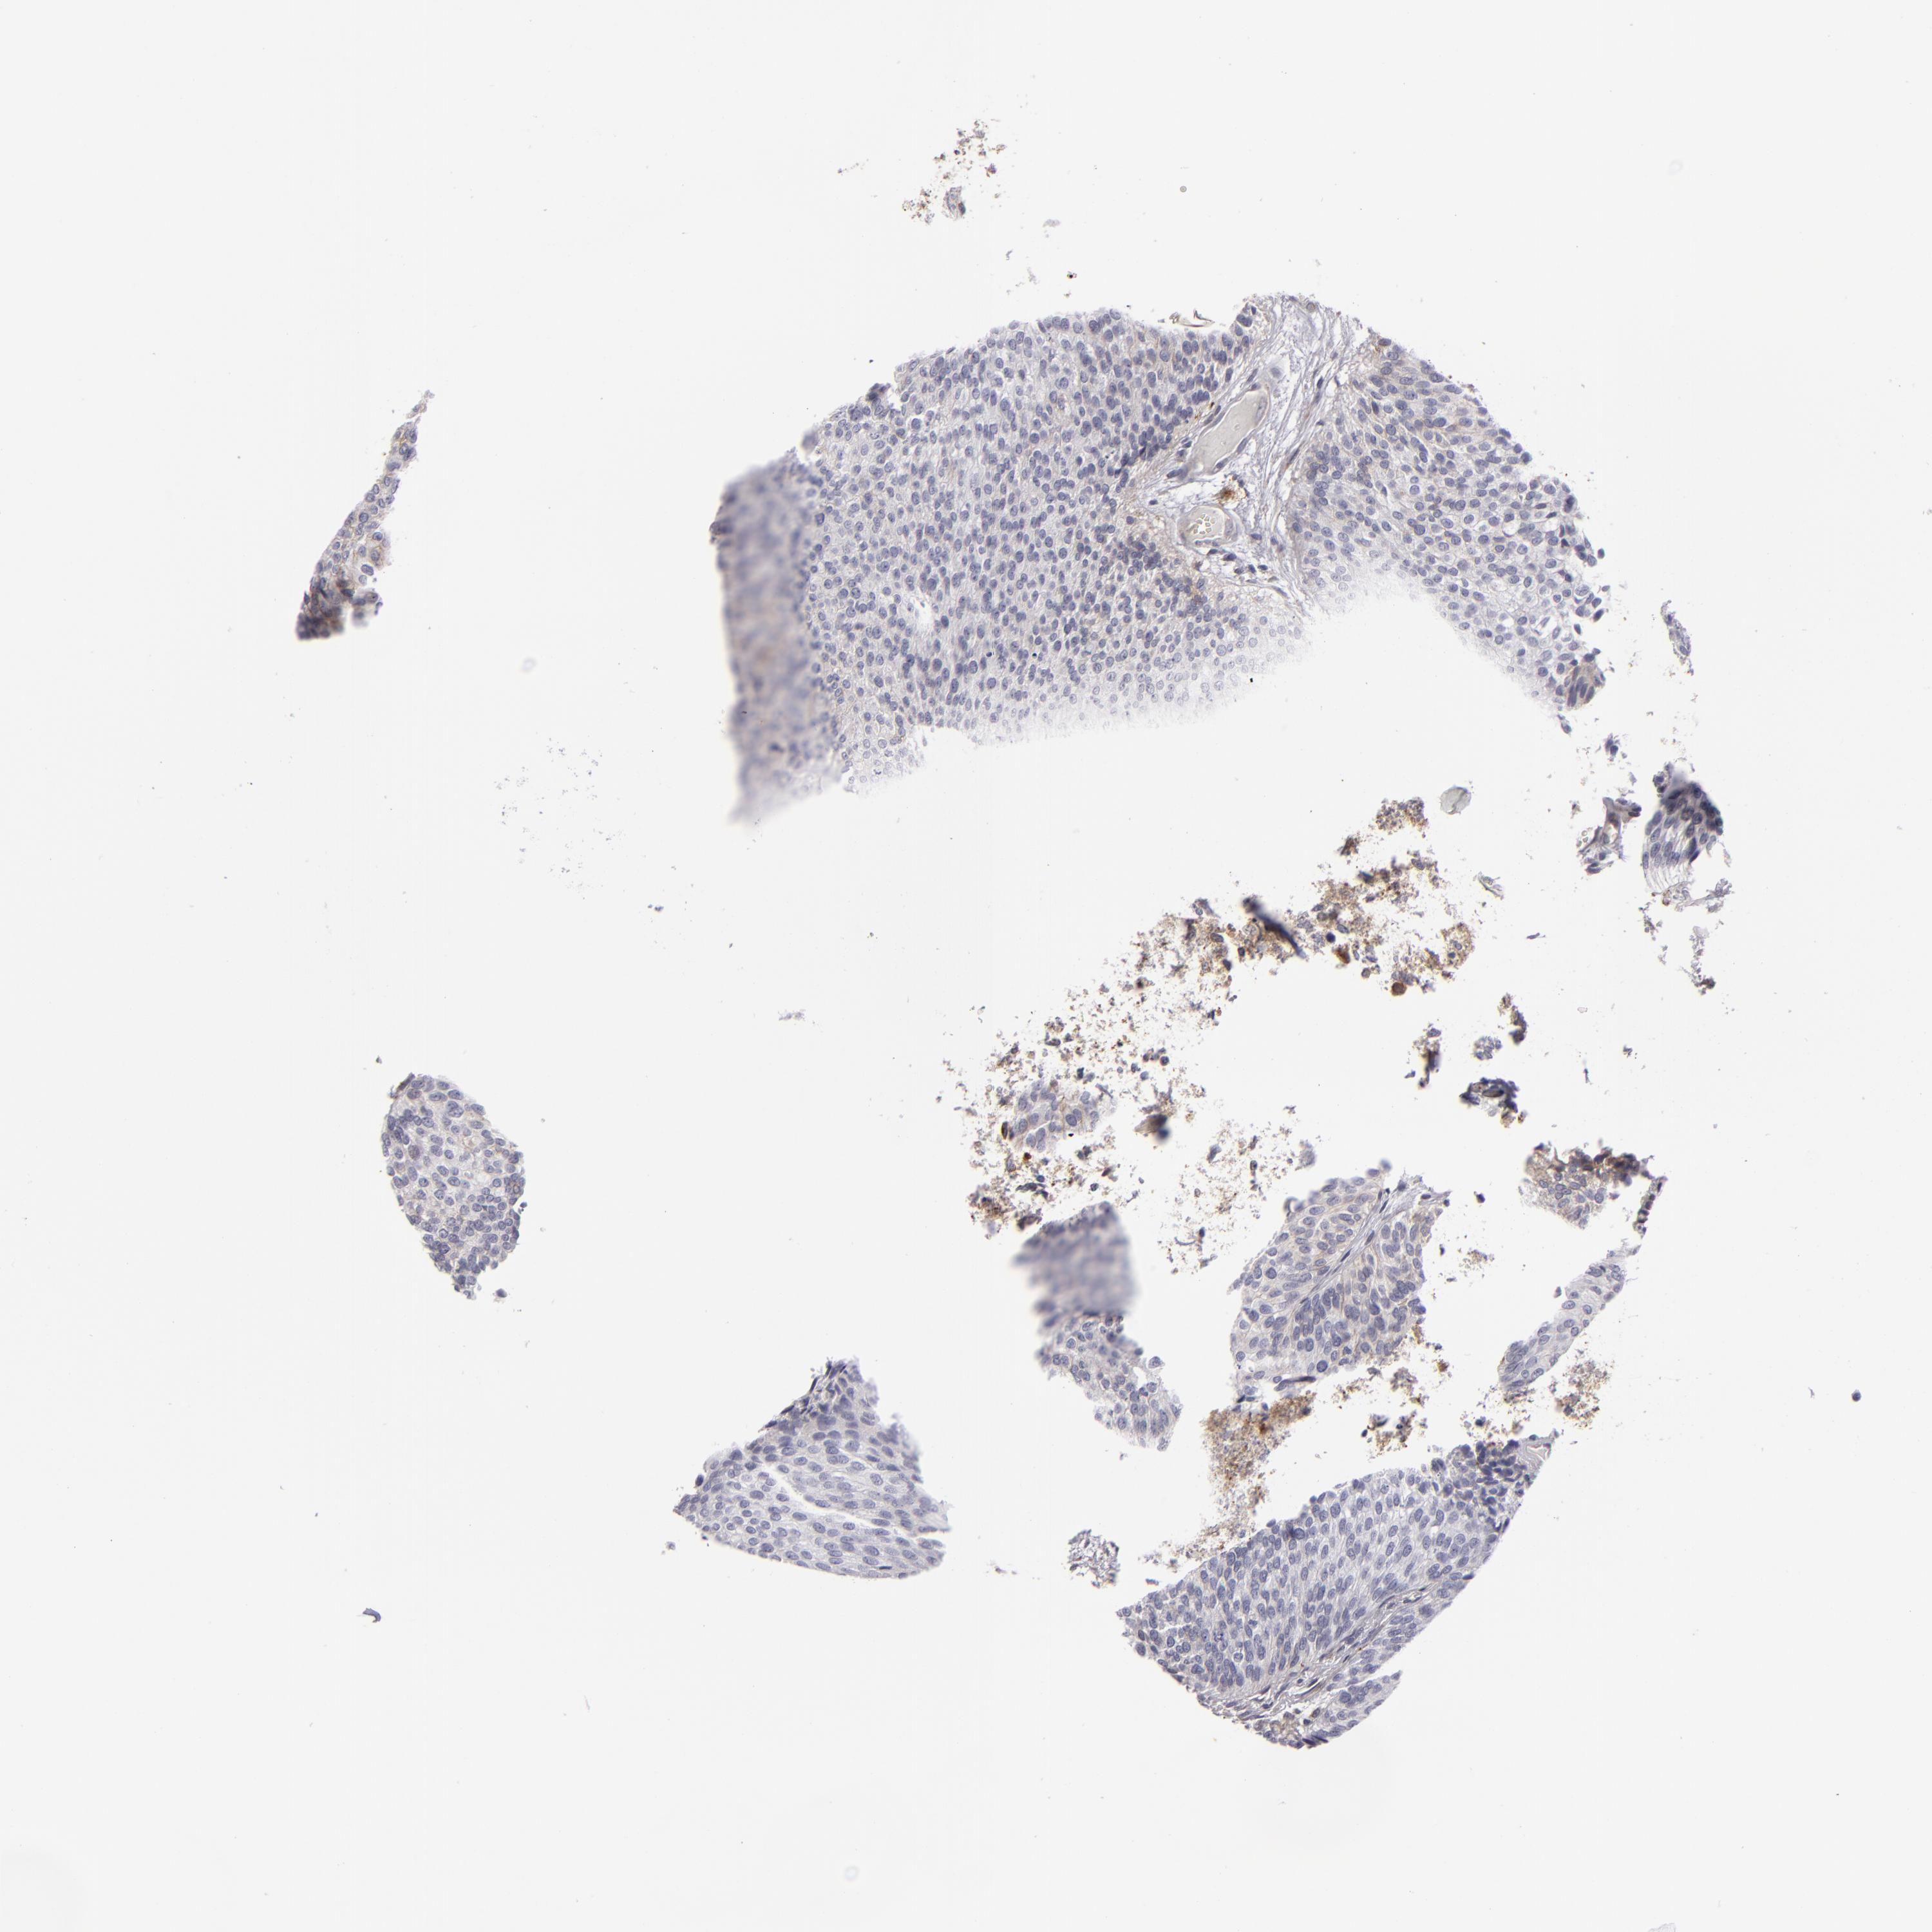

UROTHELIAL CANCER - Protein expressioni

A mouse-over function shows sample information and annotation data. Click on an image to view it in a full screen mode. Samples can be filtered based on level of antibody staining by selecting one or several of the following categories: high, medium, low and not detected. The assay and annotation is described here.

Note that samples used for immunohistochemistry by the Human Protein Atlas do not correspond to samples in the TCGA dataset.

Antibody stainingi

Antibody staining in the annotated cell types in the current human tissue is reported as not detected, low, medium, or high, based on conventional immunohistochemistry profiling in selected tissues. This score is based on the combination of the staining intensity and fraction of stained cells.

Each image is clickable and will lead to virtual microscopy that enables deeper exploration of all samples and also displays staining intensity scores, fraction scores and subcellular localization as well as patient and tissue information for each sample.

Antibody HPA010926

Antibody CAB002148

Urothelial carcinoma, Low grade

Urothelial carcinoma, High grade

Adenocarcinoma, NOS